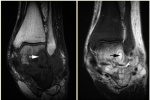

МРТ - Подострый остеомиелит: пенумбра (полутень) при внутрикостном абсцессе таранной кости

Рис. 7. OM & Abscesses: MTP Joints

МРТ - Остеомиелит и абсцессы: плюсневые суставы